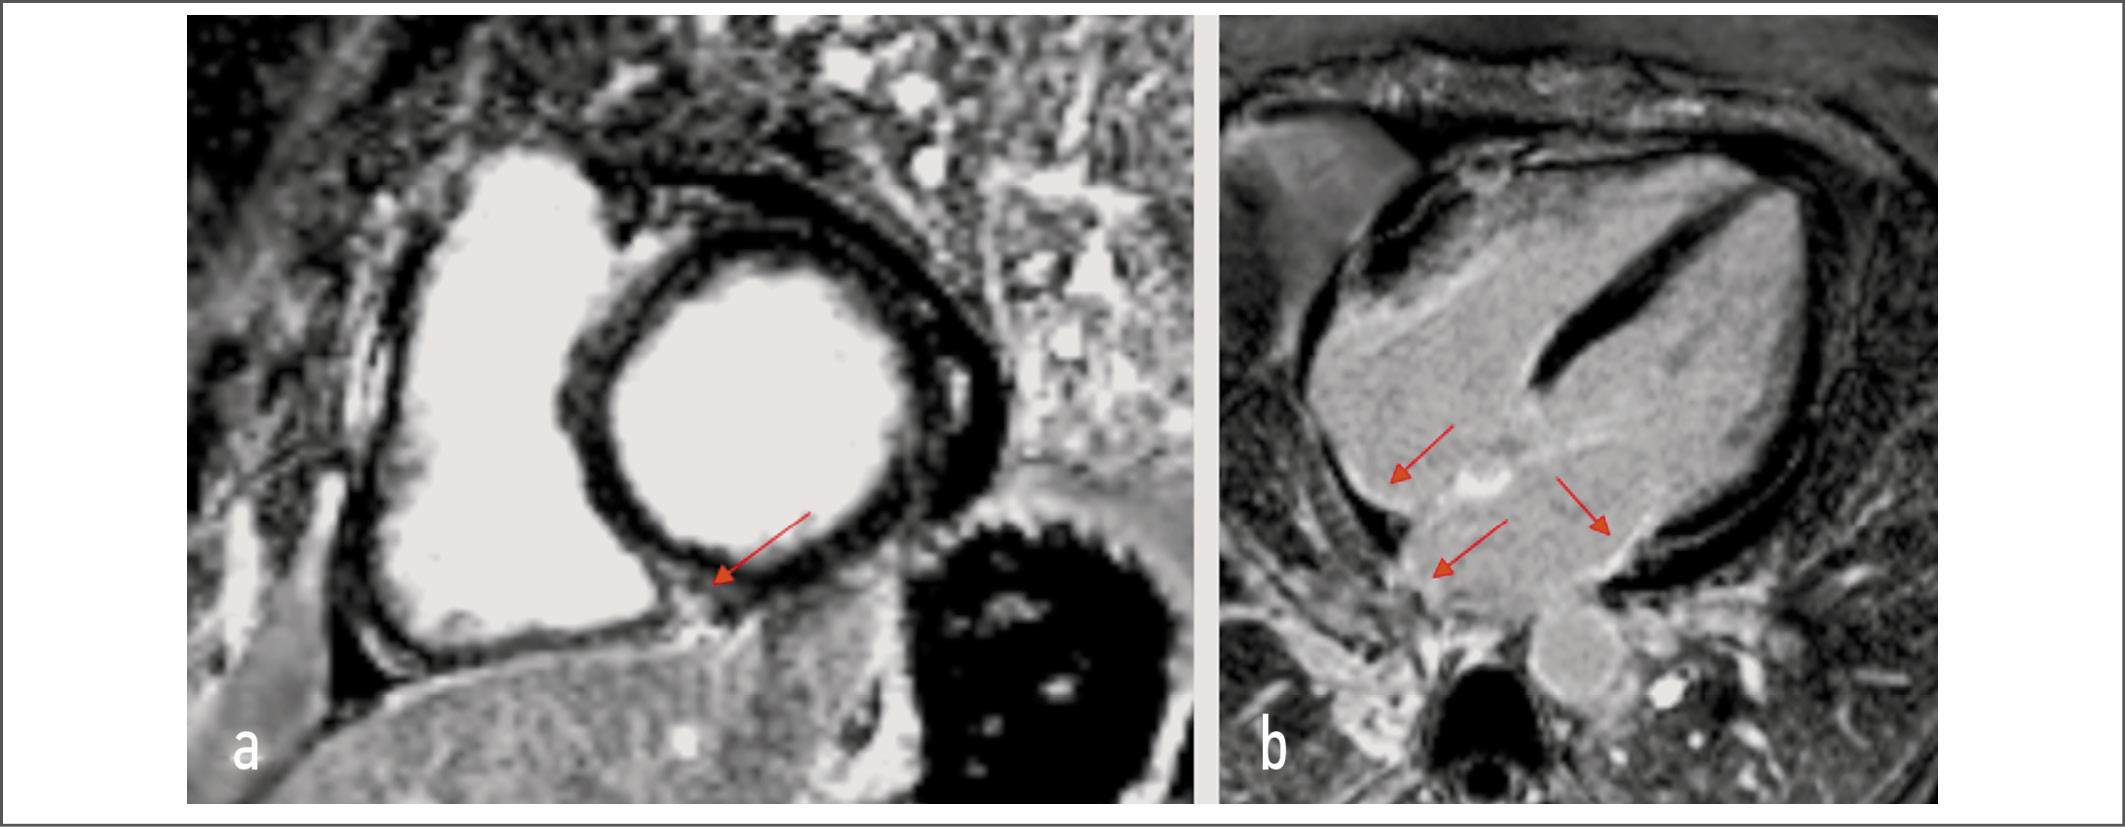

МРТ сердца с контрастированием гадолинием (24.10.2021) позволила констатировать, что толщина стенок желудочков, их сократительная способность, полости всех камер сердца соответствуют норме. На Т2-взвешенных изображениях признаков отека не обнаружено. При оценке изображений отсроченного контрастирования идентифицированы единичные участки интрамурального фиброза в МЖП по неишемическому типу. Также отмечены множественные очаги фиброза в стенках предсердий. Локальная сократимость стенок ЛЖ не нарушена. Отмечена повышенная трабекулярность эндокарда средних и апикальных отделов боковой стенки ЛЖ. Створки аортального, митрального, трикуспидального клапанов не утолщены. Тромбов в полостях сердца не обнаружено. Листки перикарда не утолщены. В полости перикарда определена свободная жидкость с максимальной толщиной полоски (11 мм) по задней поверхности ЛЖ в фазу систолы, и зафиксирован практически полный ее регресс в фазу диастолы. На рис. 4 приведены основные результаты МРТ сердца.

Рис. 4. Данные МРТ сердца пациентки В. На фрагментах представлены фазоселективные изображения «позднего» накопления контрастного вещества, полученные через 10 мин после внутривенного введения гадолиния: a – изображение по короткой оси сердца; b – изображение в четырехкамерной позиции. Стрелками указаны зоны накопления контрастного вещества миокардом ЛЖ (a) и миокардом предсердий (b).

Fig. 4. MRI data of the heart of patient B. Fragments show phase-selective images of “late” accumulation of the contrast agent, obtained 10 min after intravenous administration of gadolinium: a – the image along the short axis of the heart; b – the image in the four-chamber position. The arrows indicate the areas of contrast agent accumulation by the LV myocardium (a) and the atrial myocardium (b).

РКМП характеризуется нормальными или сниженными диастолическими и систолическими объемами одного или обоих желудочков, нормальной толщиной их стенок. Исторически считается, что систолическая функция желудочков сердца при РКМП не страдает, однако признаки латентных нарушений сократительной способности миокарда можно обнаружить у большинства пациентов. Тканевая допплерография митрального кольца может зафиксировать снижение систолических волн (s-волн), притупление формы ранних и поздних диастолических волн в зависимости от степени вовлечения в патологический процесс предсердий [16]. Оценка деформации ЛЖ по методике speckle tracking способствует выявлению скрытых нарушений систолической функции при нормальной фракции выброса ЛЖ у пациентов с патологией миокарда различного генеза [17]. РКМП характеризуется преимущественным инициальным снижением глобальной продольной деформации (что может быть связано с ухудшением функции субэндокардиальных волокон на фоне инфильтративных и фиброзных изменений), а в последующем – радиальной и циркулярной [18, 19]. В нашем наблюдении констатированы признаки латентной систолической дисфункции преимущественно в срединном и базальном сегментах переднебоковой стенки ЛЖ. Контрастная МРТ позволила обнаружить очаги фиброза в МЖП и стенках предсердий. Эти фиброзные изменения топически не совпали с полученными при анализе продольного стрейна зонами. Сочетание методов кардиовизуализации в данном случае позволило более детально оценить области лучевого повреждения миокарда, степень их выраженности и характер.